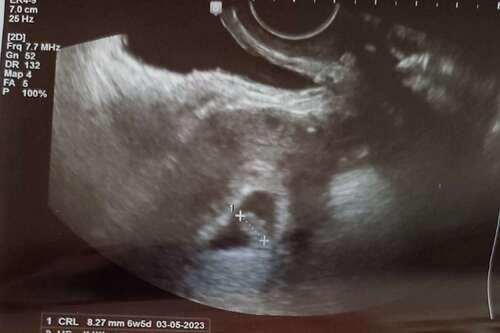

Hoi allen, hoe is het uiteindelijk bij jullie allemaal verlopen? Wij hadden gister onze eerste echo (ongeveer 6.3 wk) en onze Vk was ook wat voorzichtig met goed nieuws brengen door de vorm van de vruchtzak. Echter wel een hartslag; langzaam maar dit hoeft nog niets te betekenen met dit termijn.

Ik heb tijdens bloedverlies twee echo's gehad met een kloppend hartje. Veel stolsels ook om de vruchtzak heen in mijn baarmoeder.

Vier dagen later op de echo geen kloppend hartje meer en de vk zei toen nog dat de vruchtzak er ook niet mooi rond meer uit zag. Dus bij mij was dat helaas geen goed teken.